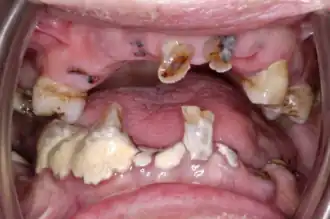

Although there is a decrease in the rate of edentulism, geriatric patients typically have high levels of plaque, calculus and debris, as they are functionally dependent on others or have lost the capacity to complete tasks such as toothbrushing thoroughly. Consequently, this results in an increased caries prevalence.[12] Dental caries is a process in which enamel is dissolved by acid producing bacteria. In 2004–2006, the average DMFT (decayed, missing and filled teeth) for adults in Australia over the age of 65 was found to be 23.7%.[12] An individual's caries risk is influenced by their sugar intake, frequency of eating, oral hygiene levels, saliva flow and function and recession. Gingival recession is a significant finding in older adults because the exposed root surface is more susceptible to root caries and therefore increases the risk for the patient. In 2015, 95.2% of Australians over the age of 75 had at least one site with gingival recession.[12] Additionally, periodontal disease prevalence was also great as 26.0% of the geriatric population was diagnosed with active periodontal disease.[12]

The most common oral conditions in geriatric patients are tooth loss, dental caries, periodontitis, dry mouth and oral cancer. Each can affect the quality of life.[23]

With continued chewing, talking, and general use, the tooth eventually wears down with attrition and dental erosion most commonly seen.[22] The outermost translucent layer, enamel, does not regenerate, so as it thins down the underlying yellowish layer, dentine, can show through or even become exposed. Aesthetically, teeth may look more yellow than white, and can become stained more easily.[20] Dentine continues to be produced, resulting in the formation of secondary dentine. Gradually however, the tubules obturate and lead to dentinal sclerosis.[20] The innermost layer containing the nerves, pulp, develops more fibres and less cells leading to shrinkage. A reduced blood supply means that an elderly patient's pulp does not have the same capacity to heal itself compared with younger patients. Calcification of the pulp with the root canals narrowing increases in frequency with the geriatric population too. This can often lead to decreased sensitivity to stimuli, e.g. cold or sweet foods. Cementum on the tooth roots is continually produced; however with age the rate this happens slows down, leaving the geriatric patient at a higher risk for developing root caries.

Elderly people who are functionally dependant and residing in residential care facilities, are particularly vulnerable to oral health issues such as periodontal disease, dental caries, particularly root caries and other oral health issues. Their dependence on staff to assist them with daily oral hygiene care often results in minimal hygiene being provided.[32] Oral health requirements are often unfortunately overshadowed by more important things such as feeding, toileting and bathing.[32] Other barriers that care staff in residential aged care facilities experience to providing oral care included lack of oral health policies, and ongoing education and training.[33]